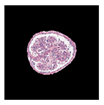

| True label: Crescentic |  |  |  |  |  |

| single-multiclass: Crescentic p = 0.999, IoU = 0.154 | |||||

| multiple-binary: Crescentic p = 1.000, IoU = 0.128 | |||||

| Spatially guided: Crescentic p = 0.979, IoU = 0.740 | |||||